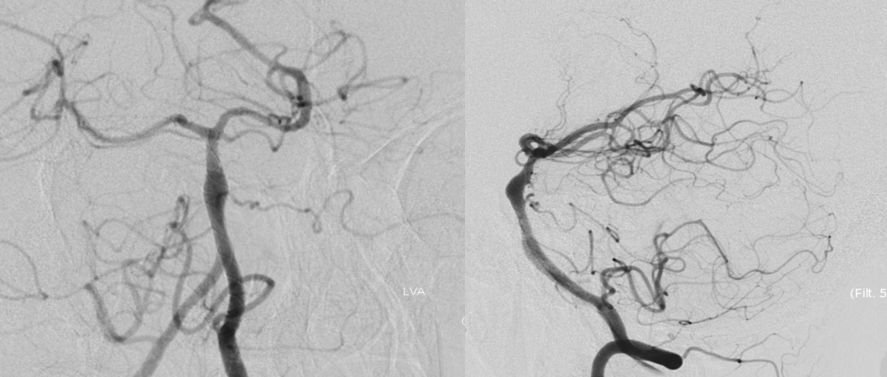

本院DSA:基底动脉巨大夹层动脉瘤,双侧后交通动脉未见明显开放(图6)。

图6